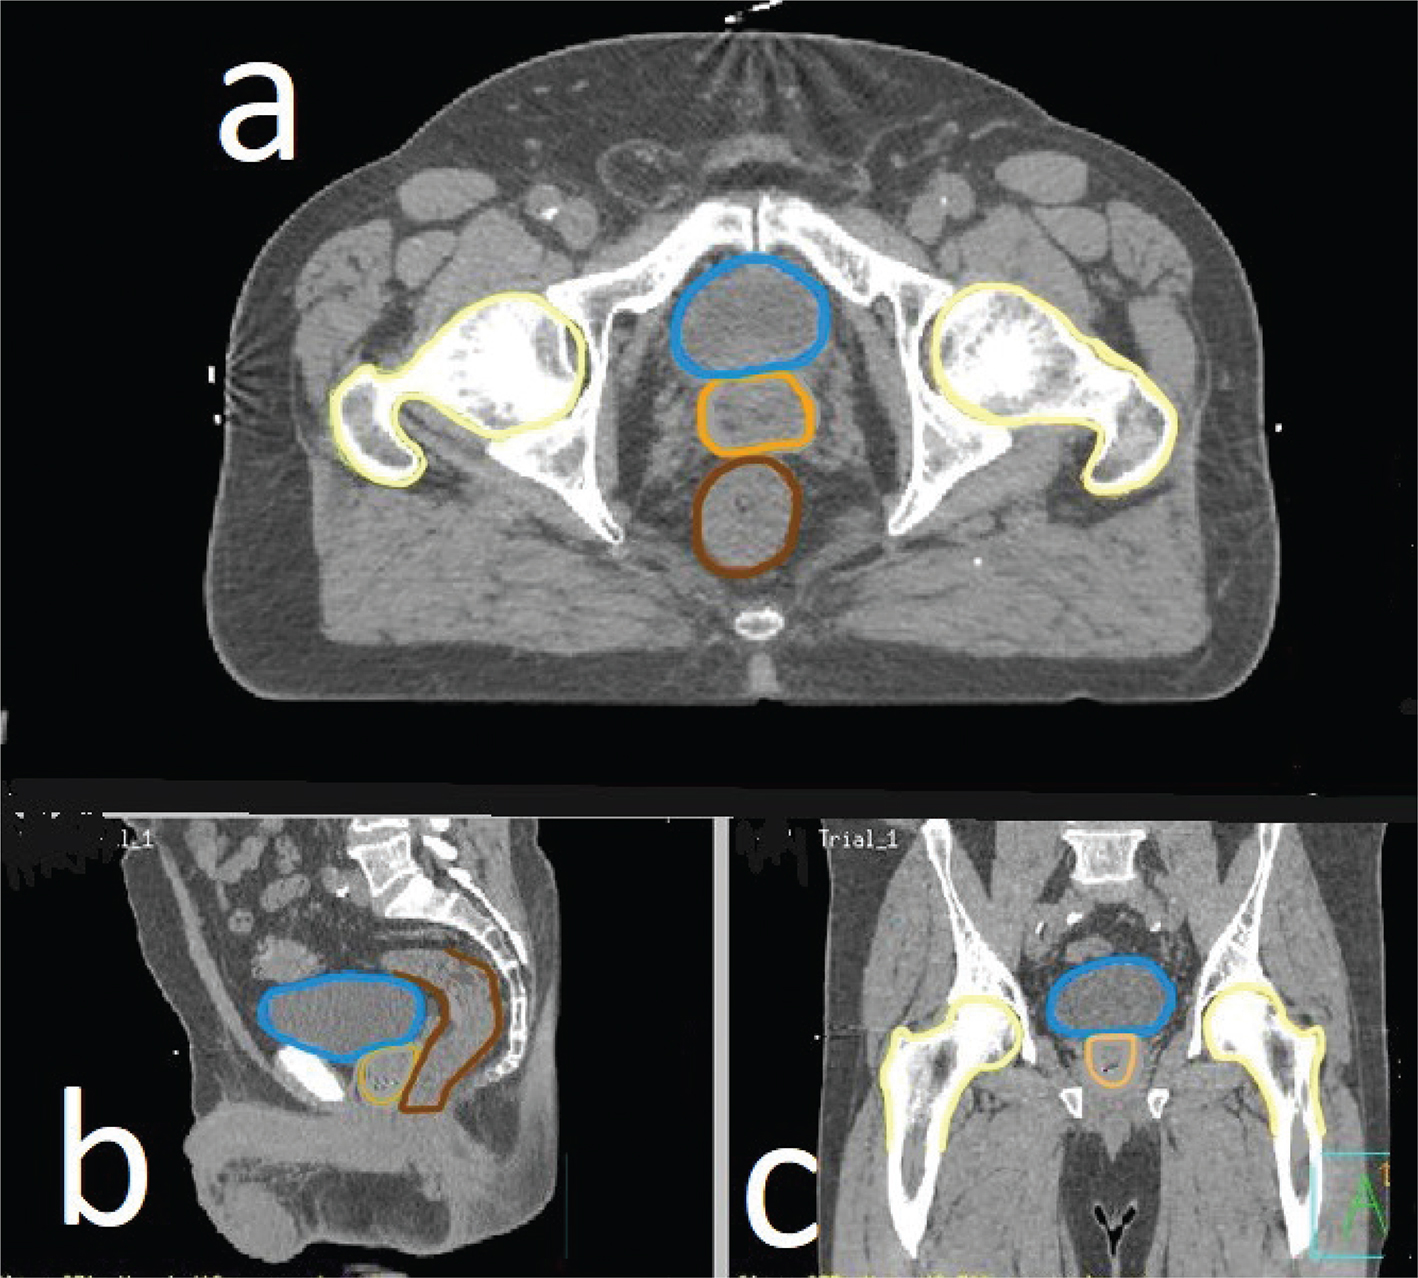

Seeking advice from allied health academic colleagues led to the consideration of the Virtual Environment for Radiotherapy Training (VERT) system (created by Vertual Ltd.), which was in use for displaying anatomical structures to radiotherapy students, who could then plan the radiation treatment of cancers in particular structures. VERT enables radiotherapy students to see their target structure (which has cancer) and the structures close to it. The premise of using radiographic images for anatomy education is not new, as it enables images to be rotated, and allows structures to be removed or made transparent so that structures of interest can be seen without any damage to them (Collins 2008). VERT displays revolveable images that are constructed from real patients’ computerised tomography (CT) scans. A specialised software takes the CT scan and constructs images that appear three-dimensional and transparent, to allow neighbouring structures to be seen (Bridge et al. 2007). With the use of VERT, no dissection of one structure is needed to view another within or behind it, as shown in Figure 1. The question was then posed: could VERT be repurposed to teach the anatomy of structures that are frequently altered by dissection, or are difficult to appreciate in two-dimensional images?

Fig 1

Figure 1. Computed tomography images (a, b and c) are a male pelvis, showing how structures are outlined in preparation for conversion into a video. Blue = bladder, beige = prostate, brown = bowel, yellow = femur bones.

De-indentified CT data of a healthy patient, free of disease, were acquired ethically for teaching purposes from a local tertiary hospital. The data were imported into a software called Pinnacle (Phillips et al., 2008) which allows structures to be digitally outlined on a CT image, and then multiple consecutive CT slices are used to create structures with a three-dimensional appearance. The anatomy team identified and traced an outline around individual anatomical structures on dozens of consecutive CT slices in Pinnacle before transferring to VERT. Figure 1a is an example of one CT slice where structures such as the rectum (brown) and hip bones (yellow) have been outlined.